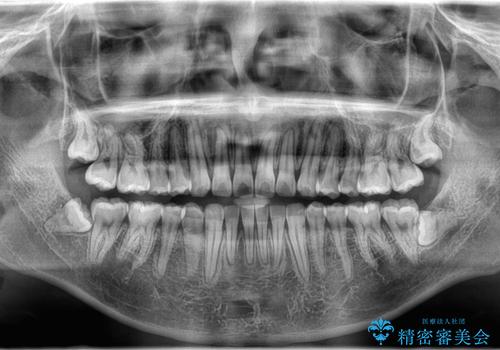

- 歯のデコボコが気になるを主訴に来院された患者様です。

インビザラインで歯は抜かずに非抜歯でデコボコを改善しました。

インビザラインで叢生の改善を行いました。

歯は抜かずに、拡大と少しのIPRで並べました。

矯正期間は半年です。